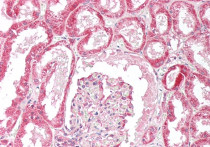

ARG64115 anti-ORP5 antibody IHC-P image

Immunohistochemistry: Paraffin-embedded Human liver tissue. Antigen Retrieval: Steam tissue section in Citrate buffer (pH 6.0). The tissue section was stained with ARG64115 anti-ORP5 antibody at 5 µg/ml dilution followed by AP-staining.